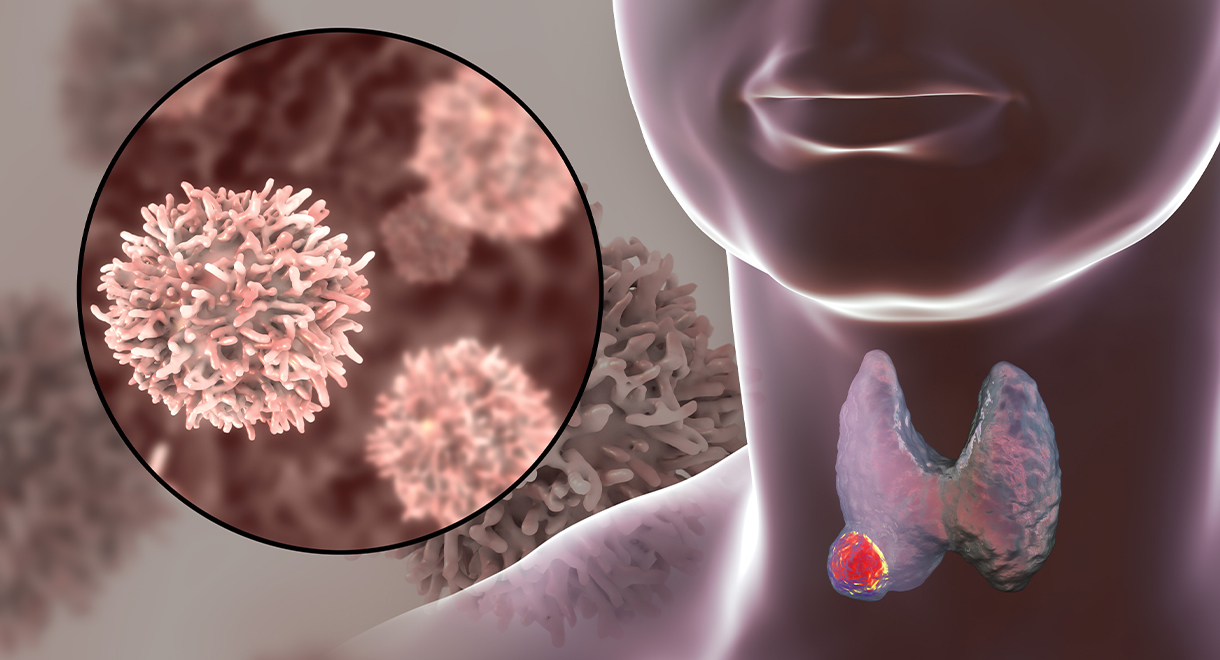

When I was first diagnosed with Thyroid Cancer it took a little while for the reality to sink in.

From the time that I had the biopsy done, receiving the news and to having the surgery, the cancer had died.

This is a very first for my Surgeon and the Pathologists. After both parties meeting to discuss my case and further treatment, the result they believe was my immune system had actually attacked the cancer and was no longer found alive.